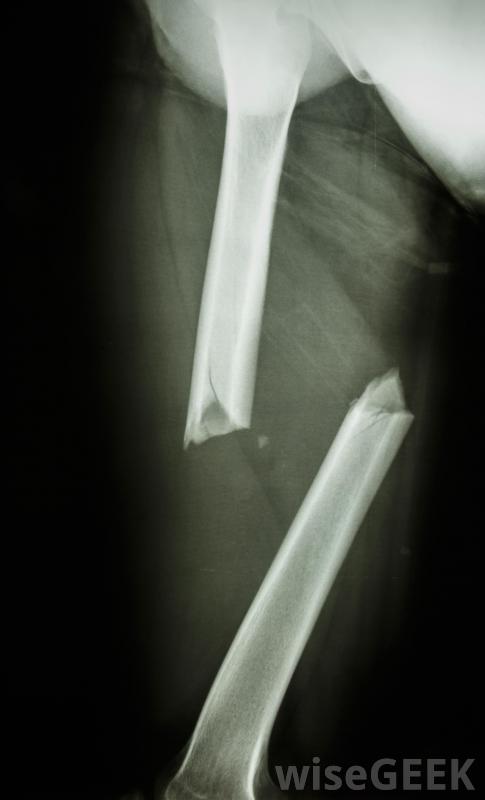

三踝骨折是踝關節骨折的一種類型。在踝關節的內側,脛骨或脛骨的下端形成一個稱為內踝的骨結節。小腿外側有一塊稱為腓骨的較薄的骨頭,在末端形成一個稱為外踝的腫塊,或第三踝,是由脛骨下端后部的一個骨唇形成的。當踝關節骨折涉及三個踝關節時,稱為三踝骨折,通常需要手術將骨折固定在一起,同時愈合跌倒是老年人三踝骨折的常見原因,可能是由于摔倒、突然扭傷或扭傷腳踝引起的。也可能是車禍造成的,以及其他小腿受傷。由于踝關節由許多不同的骨骼組成,踝關節骨折的嚴重程度從一塊骨頭的裂縫到幾塊骨頭的斷裂,有時刺穿皮膚疼痛,腫脹,瘀傷,可能會出現畸形,腳踝可能無法承受重量。跌倒可能導致三踝骨折如果在檢查可能骨折的踝關節時發現這些癥狀,可能會懷疑骨折。然后可以進行X光檢查,以提供準確的診斷。在某些情況下,只有內踝或外踝可能骨折。如果骨骼不太遠,骨折被認為是穩定的,這意味著骨折會繼續存在當骨頭重新排列時,可能不需要手術,治療可能包括石膏或夾板。如果是三踝骨折或雙踝骨折,內踝和外踝骨折,則損傷通常不穩定,通常需要手術三踝骨折可導致瘀傷。三踝骨折的外科治療通常包括使用當骨折愈合時,用來固定骨折的金屬板、螺絲釘或金屬絲。在骨折牢固融合在一起之前,腳踝不可能承受重量,這可能需要四個月的時間,在這段時間里可以拍X光片來檢查骨骼是否沒有移位,一旦有可能移動腳踝,建議進行一系列的鍛煉來加強關節周圍的肌肉通常會對骨折進行X光檢查三踝骨折的外科治療通常包括使用金屬板和螺釘或金屬絲將骨折固定在一起鞋子有助于防止許多三踝骨折。腳踝骨折可能是由于突然轉動腳踝造成的在腳上放置石膏可能是治療三踝骨折的一部分。